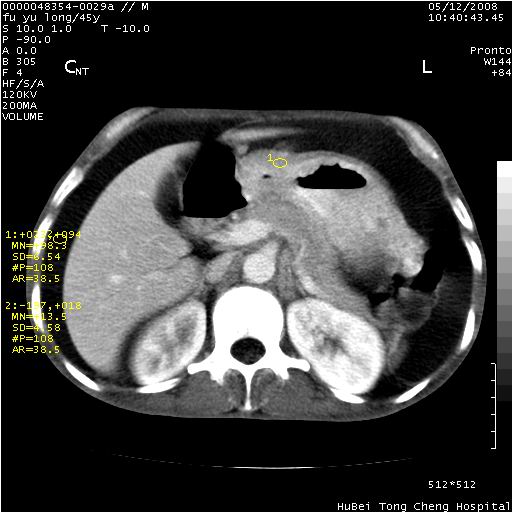

以下是引用医影拾贝在2008-5-30 2:38:00的发言:[br]气肿性胃炎、胃十二指肠溃疡、腹膜炎,考虑穿孔可能性较大

以下是引用lkc8963在2008-5-30 8:44:00的发言:[br]胃窦癌伴网膜(胃结肠韧带)/腹膜及腹膜后淋巴结转移.